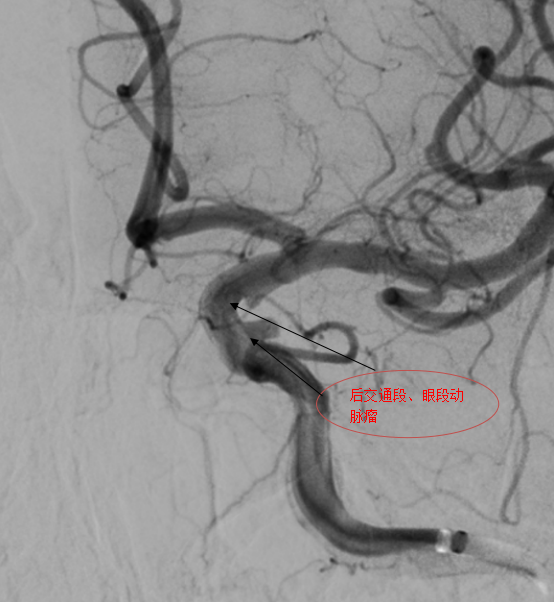

第一例手术的患者确诊为眼动脉动脉瘤合并后交通段动脉瘤,属于多发复杂动脉瘤,治疗难度倍增。团队通过置入血流导向后,动脉瘤内即可形成造影剂滞留,手术过程30分钟,患者术后2天出院。